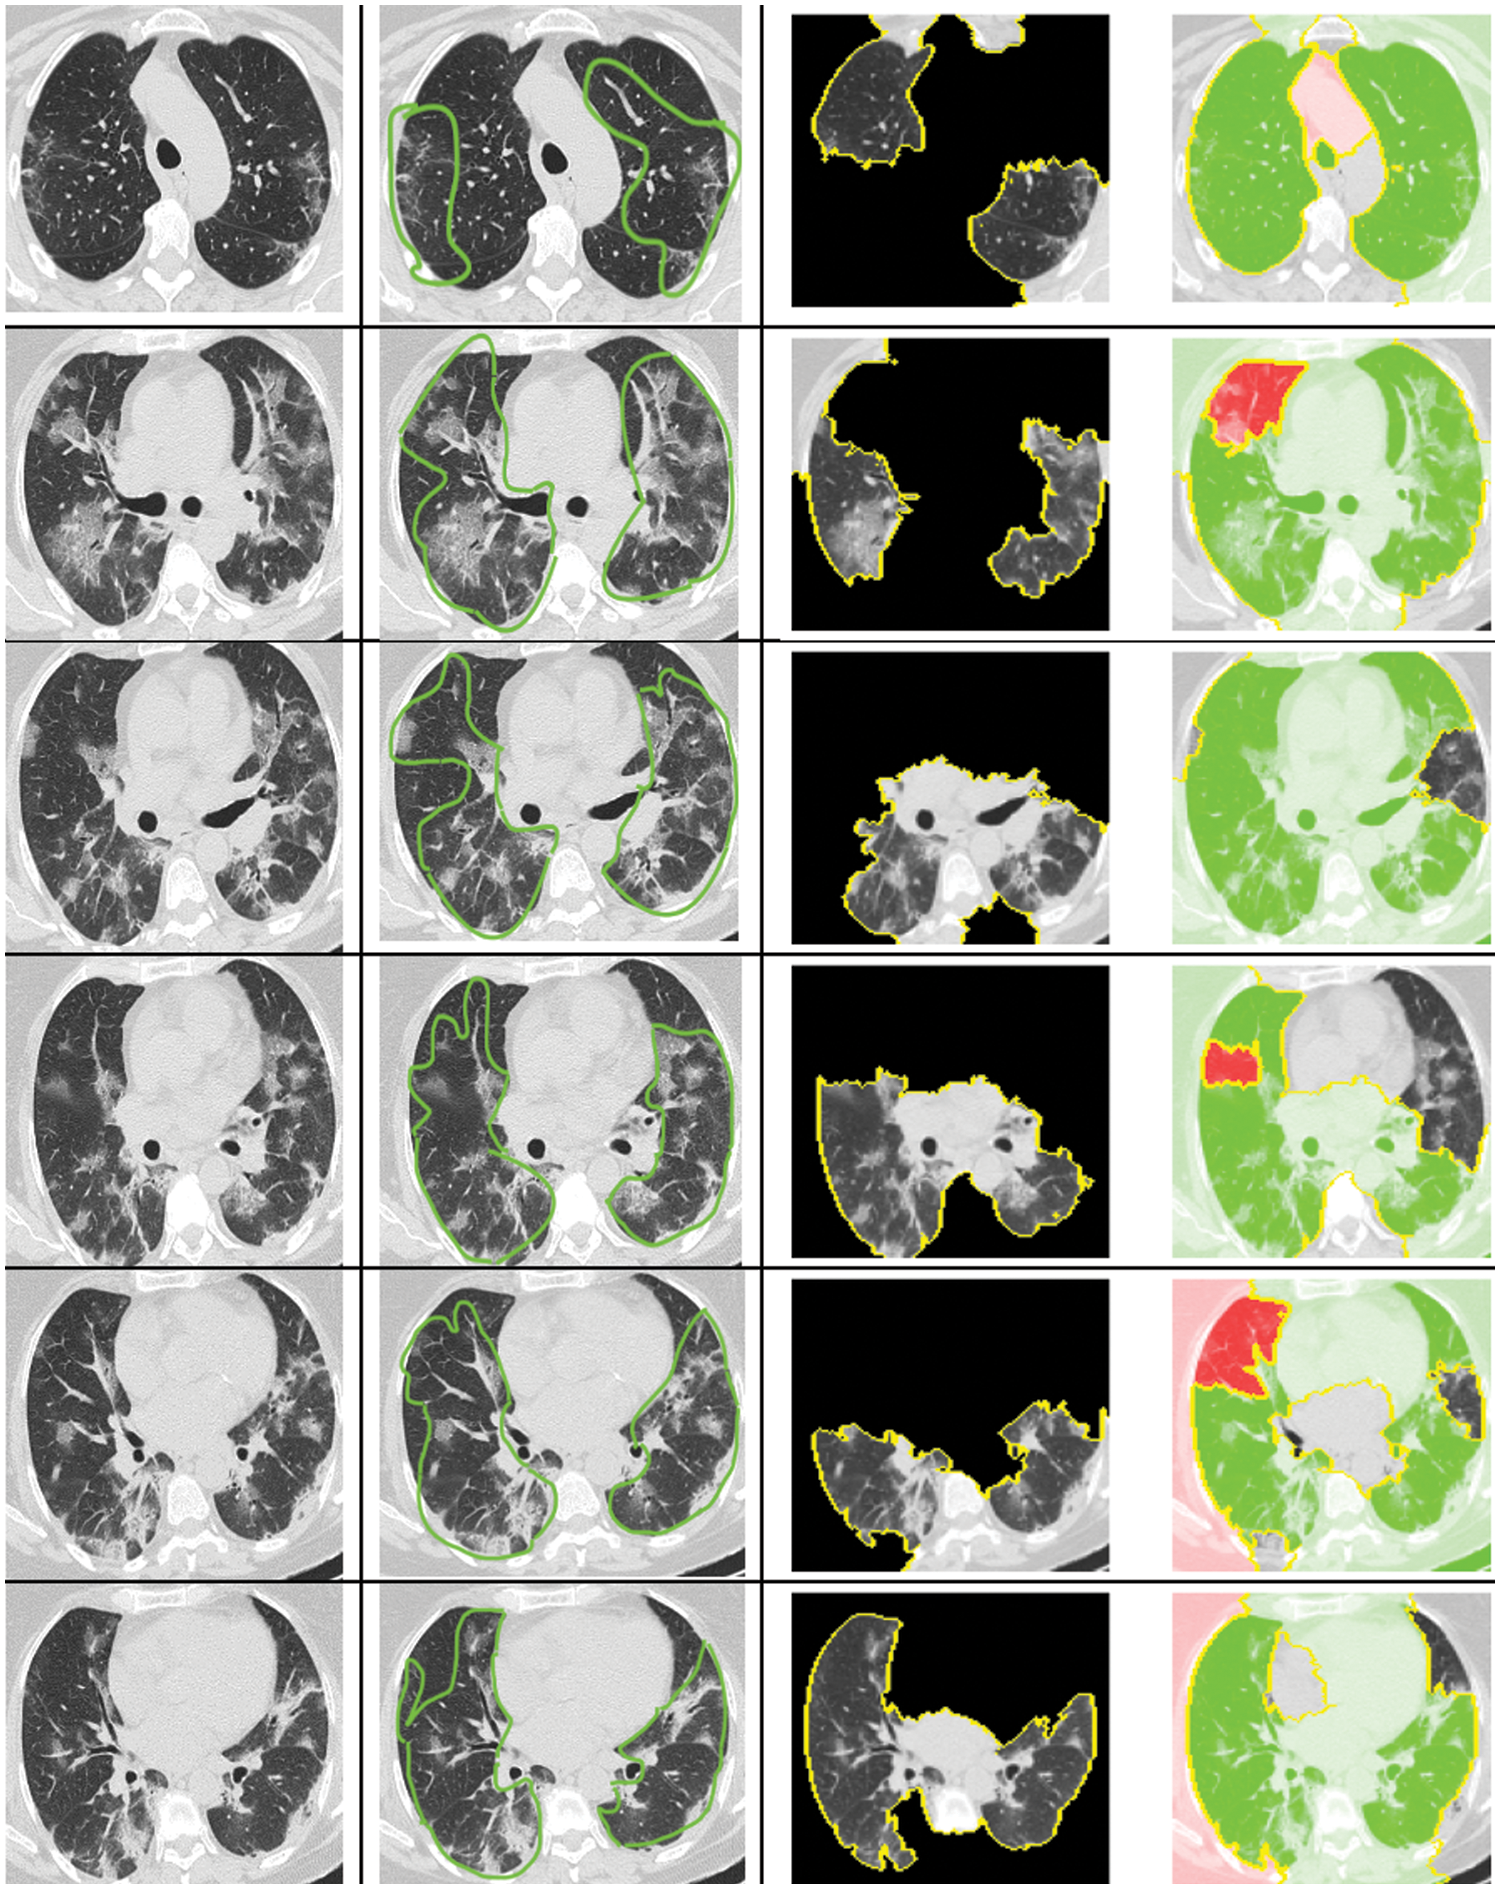

In the medical domain, physicians and professionals often seek to understand why a patient is diagnosed as COVID-19 positive, in addition to simply classifying the patient as suffering from the virus. We applied an XAI approach to justify the classifications achieved using CT-Scan images. Our goal was to elucidate the decisions made by our automated computational method for each patient. For this purpose, we employed the LIME approach to explain the classification outcomes generated by the deep neural network used in our study.

The CT-scan images presented in Fig. 10 illustrate the original input CT-scan image alongside the regions of interest that led to a COVID-19 classification. The first column in Fig. 10 shows the actual CT-scan images inputted into our automated deep learning system. A typical radiologist would look for the following imaging characteristics in COVID-19 cases through CT scans:

Figure 10: Explanation for the decision of classifying as COVID or non-COVID using LIME

• Ground-Glass Opacities (GGOs): These appear as hazy, opaque areas that do not obscure the underlying lung structures and are a common early finding in COVID-19.

• Bilateral and Peripheral Distribution: COVID-19 often affects both lungs, with abnormalities more commonly found along the outer edges.

• Multifocal Involvement: Multiple lung areas are often involved, indicated by several patches of ground-glass opacities.

• Consolidation: In severe cases, ground-glass opacities may progress to consolidation, where the lung tissue becomes more solid.

• Crazy-Paving Pattern: This is identified by ground-glass opacities with superimposed interlobular septal thickening and intralobular lines.

• Vascular Enlargement: This is seen as enlarged blood vessels in the CT-scan image, part of the inflammatory response.

• Absence of Features Typically Seen in Other Respiratory Diseases: Such as the lack of pleural effusions, lymphadenopathy, and cavitation.

As shown in column 2 of Fig. 10, the highlighted regions satisfy the majority of these characteristics. These annotations were made by a professional radiologist without prior knowledge of the patients’ COVID-19 status. Intriguingly, our computational approach accurately diagnosed these patients, and the XAI identified the correct region in the CT-scan image that a radiologist would find relevant.

The XAI process segments the raw CT-scan image into several partitions worthy of investigation. It then produces an image highlighting only the region of interest, as seen in column 3 of Fig. 10. This region contributes significantly to identifying a patient as COVID-19 positive using our automated approach. The identified region of interest aligns with what professional radiologists would consider a significant indication of COVID-19. Notably, the LIME approach emphasized the regions showing GGOs, leading to the classification of the patient as COVID-19 positive. Furthermore, the regions of interest annotated by the radiologist were also deemed important by the XAI approach.

What stands out in this analysis is that the LIME methodology appears to produce results that largely align with the regions marked by the radiologist, suggesting a high degree of accuracy. This alignment is crucial, as it not only validates the model’s diagnostic capabilities but also enhances radiologists’ trust in the AI system, providing a clear and interpretable rationale for its decisions. Such interpretability is essential in a clinical setting, where understanding the basis for AI-driven conclusions can directly inform patient care decisions and strategies.